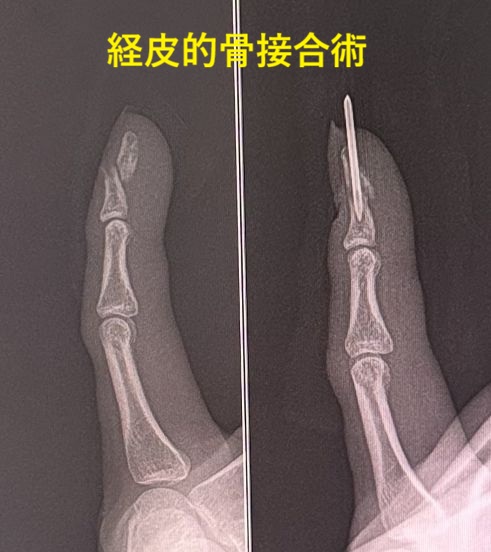

| 中手骨骨折は、骨端線離開・基部骨折・骨幹部骨折・頚部骨折に分かれます。頚部骨折は別名、ボクサー骨折と呼ばれ高頻度に認められます。 治療 転位(ずれ)がなければ、簡単なアルミニウム副子固定、ナックルシーネ固定、ギプス包帯で固定します。転位のある症例は徒手整復(牽引などして元の状態に戻す手技)してナックルキャスト固定をします。しかし整復しても直ちに再転位する症例は経皮的骨接合術(皮膚の上からピンなどで固定)を行います。整復不能な症例は内固定術(皮膚切開してピンやプレート固定)を行います。 |

| 基節骨骨折は、骨端線離開・基部骨折・骨幹部骨折・頚部骨折・骨頭骨折に分かれます。骨端線離開や基部骨折、剥離骨折は見逃されやすく、ストレスレントゲン撮影が必要な場合が多々あります。 治療 転位がなければ、バディテーピングやアルミニウム副子固定、ギプス包帯などを行います。転位があればナックルキャストやナックルシーネ固定、徒手整復してギプス固定をします。しかし、整復しても再転位する症例は経皮的骨接合術を行います。徒手整復が不能であれば切開して内固定術を行います。 |

| 中節骨骨折は、掌側板剥離骨折・骨端線離開・基部骨折・骨幹部骨折、骨頭骨折・頚部骨折に分かれます。最も外来でよく遭遇する骨折はPIP関節(指先から2番目の関節)の過伸展によって発生する掌側板剥離骨折です。なお、転位のない掌側板剥離骨折、基部骨折の症例は見逃されやすいので要注意です。また、ストレスレントゲンで診断されることが多々あります。 治療 転位がなければ、バディテーピングやアルミニウム副子固定、プラスチックギプス固定などを行います。整復されても再転位する症例はナックルキャスト固定、経皮的骨接合術、骨接合術を行います。 |

| 末節骨骨折は、指先に物が落ちたり、車のドアに挟まれて受傷されます。大半は爪の損傷を認めます。軽度な骨折もありますが、粉砕骨折も見受けられます。診断の際には受傷した状態を再現するストレスレントゲン撮影で骨折が判明されることもあります。小児では成長線部で剥離骨折、骨端線離開によく遭遇します。 治療 軽症例では、プラスチックシーネやアルミニウム副子固定などを行います。転位が著しい症例や関節内骨折では経皮的骨接合術が行われます。なお転位が著明にもかかわらず、患者さんの希望で長期間固定して骨癒合した症例もあります。 |